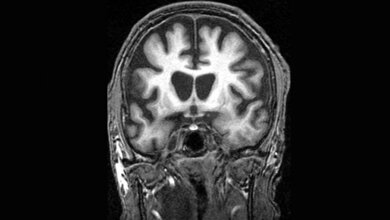

Die Erkrankung Chorea Huntington zeichnet sich durch zunehmende, nicht kontrollierbare, teils „einschießende“ Bewegungen aus („Veitstanz“). Neben dieser Bewegungsunruhe leiden Betroffene an schweren kognitiven Beeinträchtigungen und psychiatrischen Symptomen. Die meisten erkranken in jungem Alter, etwa 20 Jahre nach dem Ausbruch endet die Huntington-Erkrankung dann tödlich. Grund dafür ist eine spezifische Veränderung im Huntingtin-Gen, die mit einer Wahrscheinlichkeit von 50 Prozent vererbt wird. Genetisch kommt es zu wiederholten Verlängerungen eines kleinen Abschnitts im Huntingtin-Gen, zu sogenannten CAG-Repeats. Diese verursachen eine Verklumpung von Huntingtin in den Nervenzellen, was sie unwiderruflich zerstört.